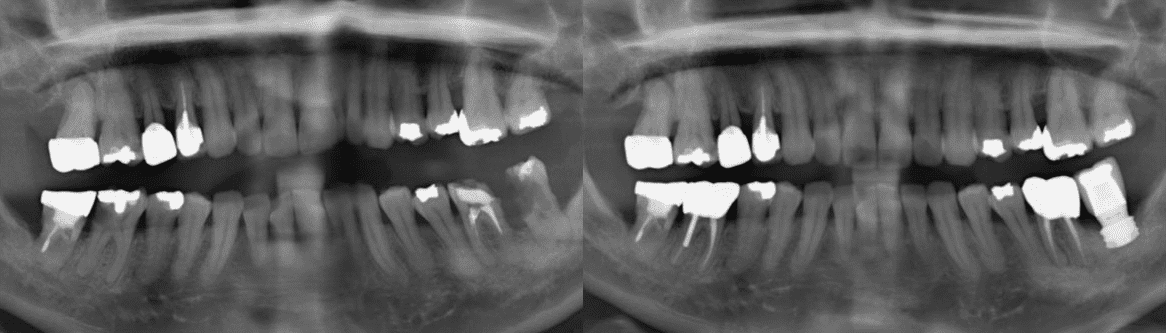

한꺼번에 많은 치아를 발치하고 여러개의

임플란트를 심는 경우부터 간단한 스케일링까지